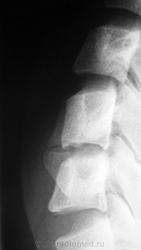

Дело в том, что именнов этом ПДС, определяется фиксация и ограничение объёма движений. Как видите - ни при згибании, ни при разгибании ширина и форма межпозвонкового диска не изменяется. Да и форма тела С5 мне кажется весьма отличной от других тел... Такое впечвтление, что сформирован неоартроз.

Там действительно есть неоартроз с деф артрозом, но  это точно не сами позвонки, а части избыточно развитых отростков...

Спасибо Анатолий Иванович, понял что это гиперплазированные поперечные отростки тел С5 и С6, с сформированым между ними неартрозом и деф. артрозом. Вообще эта пациентка какаято странная - жалуется на похудение одной (правой) половины тела. Напрвляли её на ПКОП - ничего кроме сколиоза, с небольшим торсионным компонентом нет. Тут вот шейный отдел, надо бы грудной снять, а тут опять кто то из врачей сказал, что много уже рентгена и на грудной не направили...